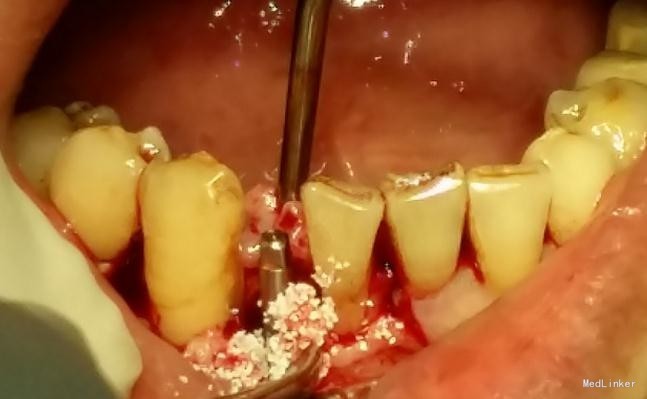

患者,男,45岁,右侧下颌侧切牙严重龋坏,拔除后要求种植修复,平素体质一般,无药物、食物过敏史,无高血压、心脏病等系统病史

牙科CT检查骨量适中,适合种植

种植修复

效果很好,患者满意